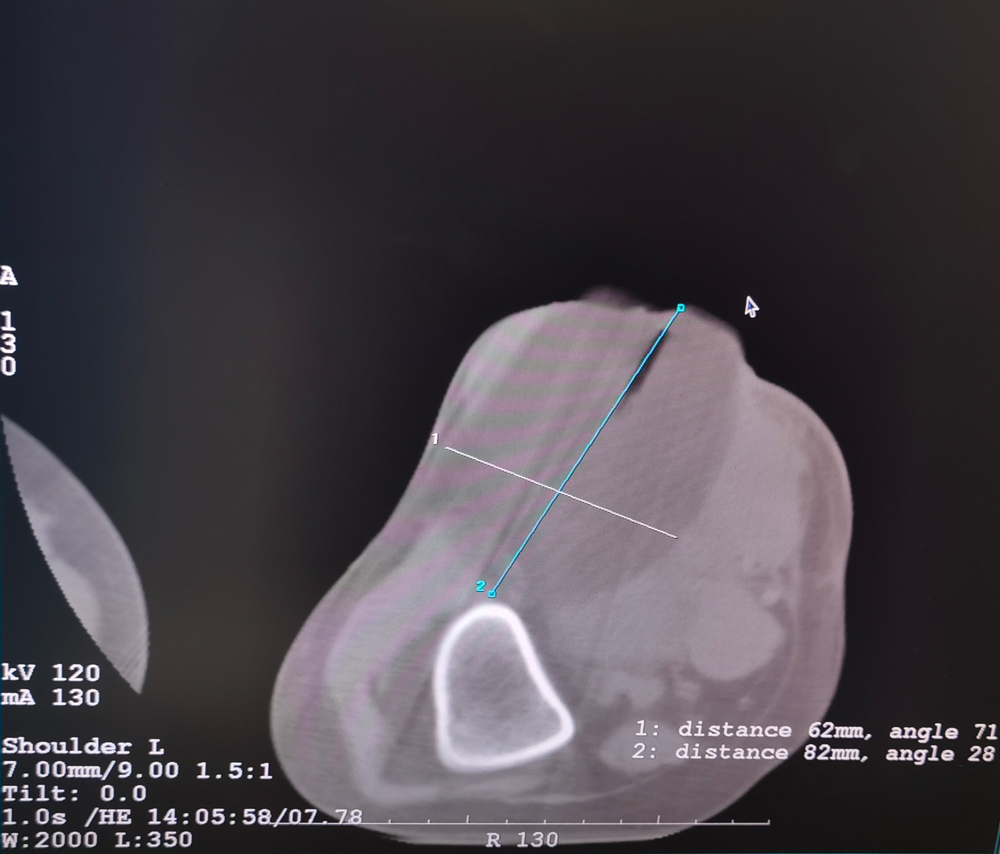

女,42歲,復(fù)發(fā)性脂肪瘤,病灶位于右側(cè)膝關(guān)節(jié),直徑大小13cm。采用雙針方案,共進(jìn)行6個凍融循環(huán),最大冰球直徑達(dá)8.2cm,術(shù)中多方位治療全面覆蓋病灶范圍。患者術(shù)后狀況良好。